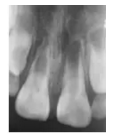

X線片示:11根管短小且粗大,根尖孔未閉合,管壁呈平行狀,根中1/3見內吸收,牙根發(fā)育7期,根部未見根折線,根尖周有稀疏區(qū);21根部發(fā)育程度與11相同,根部未見根折線及內外吸收,根尖周未見明顯稀疏區(qū)(圖1a)。

圖1a 術前X線片